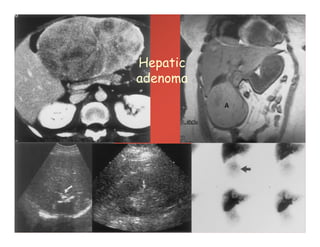

Hepatic

adenoma